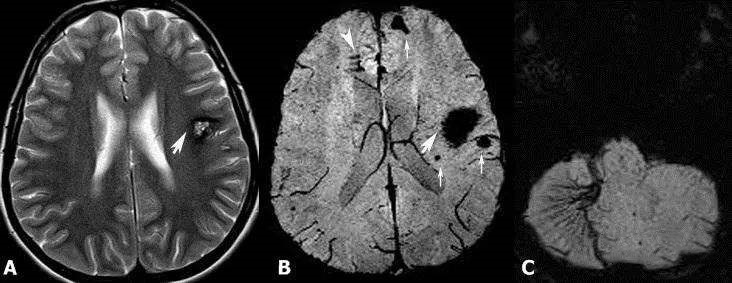

诊断脑海绵状血管瘤主要依靠影像学检查。以下是几种常用的诊断方法:

海绵状血管瘤MRI(图源见水印)

2.计算机断层扫描(CT):CT扫描可以显示血管瘤的钙化情况,但不如MRI敏感。对于某些患者,CT可能作为初步筛查工具。